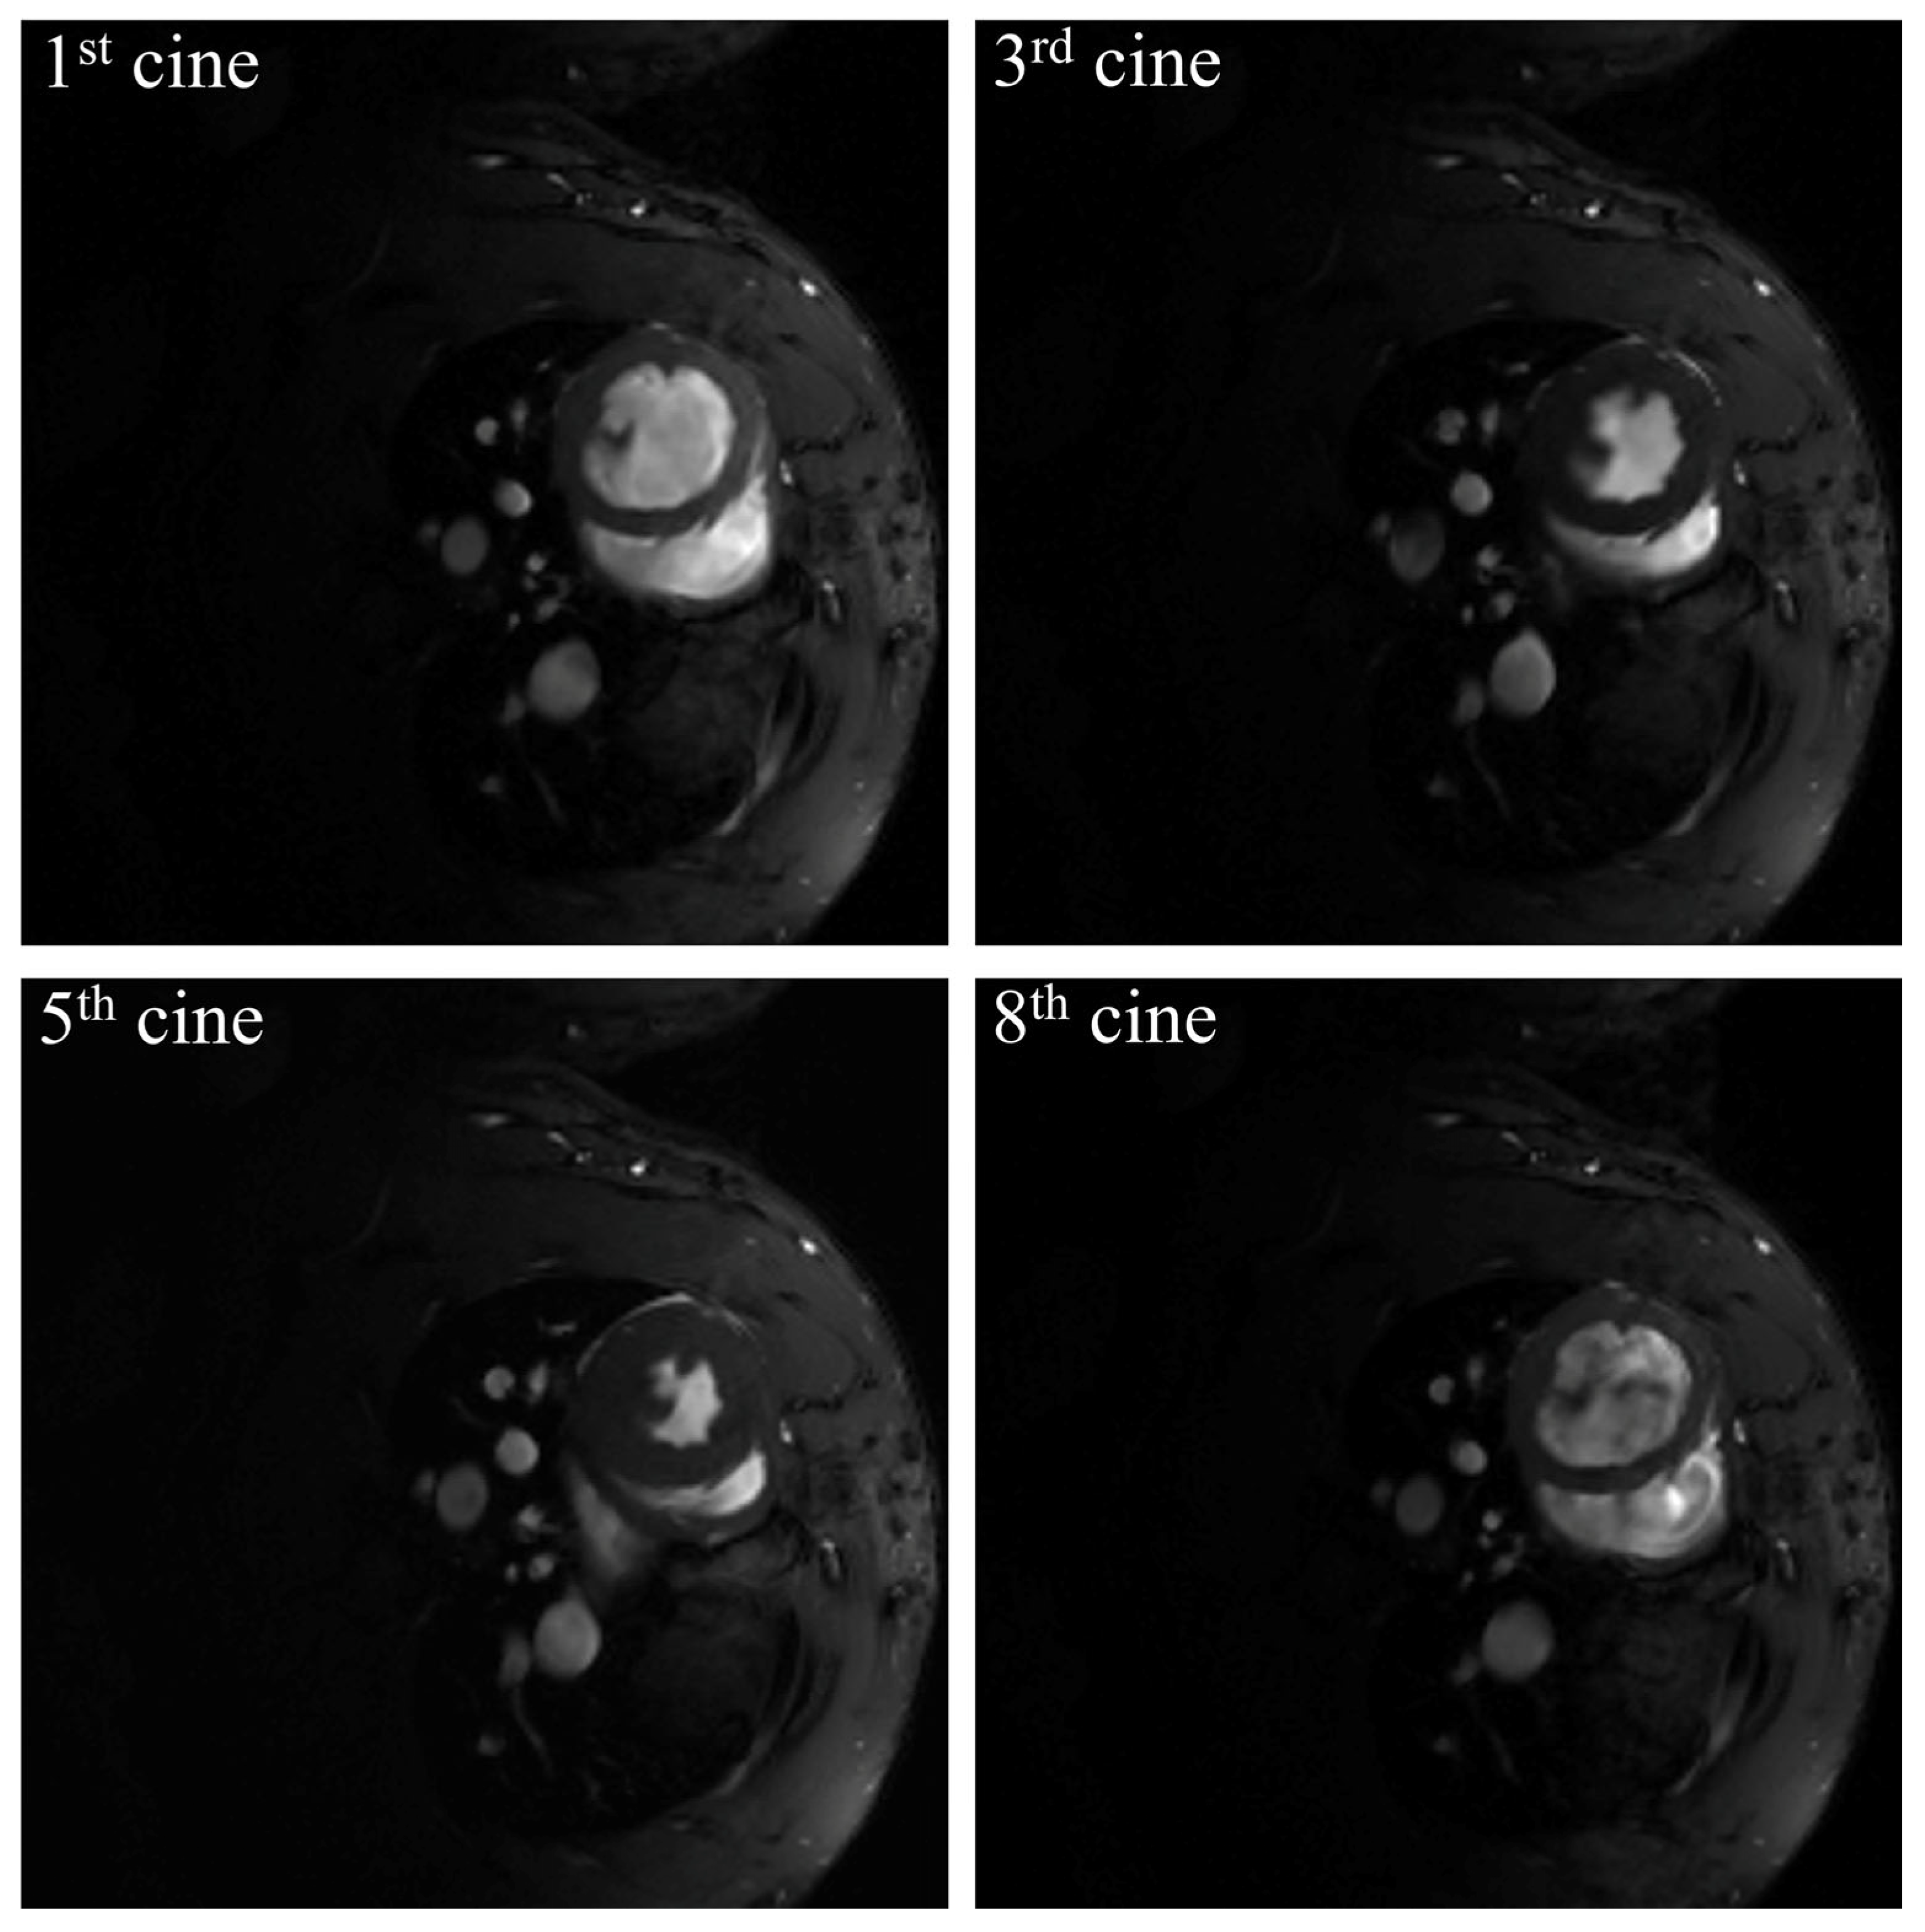

2.1. Cine MR Image of Rat Cardiac Data